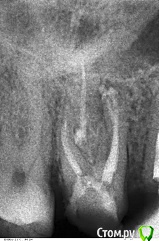

Весна2009 Опубликовано 30 января, 2017 Автор Поделиться Опубликовано 30 января, 2017 И снова здравствуйте!Уважаемые доктора! Кто был в теме или присоединится вновь, пожалуйста, можно выдвинуть какую-то версию.16 зуб залечили каналы, поставили постоянную пломбу. 5 января это было. Но до сего дня зуб болит. Может это не сам зуб, а десна? Ночью не болит, по-крайней мере, не чувствую. Как только просыпаюсь, начинает по-баливать, сначала не сильно, дальше, сильнее. Боль терпимая, но очень надоело. Иногда сильно болит. Редко почти не болит. 15 удалили. Поставили имплант. Хирург посчитал, что можно, про боли в 16 ему было известно.Что и по какой причине может болеть в перелеченном зубе?Всем спасибо Ссылка на комментарий

Весна2009 Опубликовано 30 января, 2017 Автор Поделиться Опубликовано 30 января, 2017 Снимок Ссылка на комментарий

Весна2009 Опубликовано 30 января, 2017 Автор Поделиться Опубликовано 30 января, 2017 Размер пришлось уменьшить,н е загружалось, качество стало хуже Ссылка на комментарий